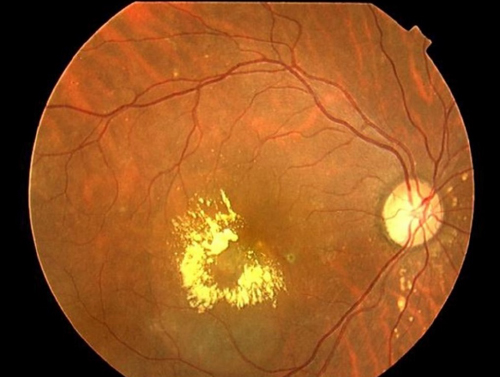

加齢黄斑変性

加齢黄斑変性とは

黄斑(おうはん)の変性によって視力が低下する疾患です。

黄斑は物を見るために最も大切な網膜の中心部にあり、文字を読んだり、顔を認識したり、色を感じたりする視力の中心となる部分です。

この病気では、黄斑の裏側にある脈絡膜に新生血管(異常血管)が発生することで黄斑が変性し、視機能が障害されることによって生じます。

症状

物の中心がかすんで見えたり、ゆがんで見えたり、黒く欠けて見えたりします。わが国の成人失明原因の第4位です。

治療

抗VEGF(血管内皮成長因子)抗体製剤の硝子体内注射が導入され、異常血管の成長を抑える働きがあり、進行の抑制や視力回復が期待できます。複数回の治療を要することが多いです。

当センターでも、この治療を保険診療で行っています。

定期検査の流れ、サプリメントや生活習慣の注意点などもご提案します。